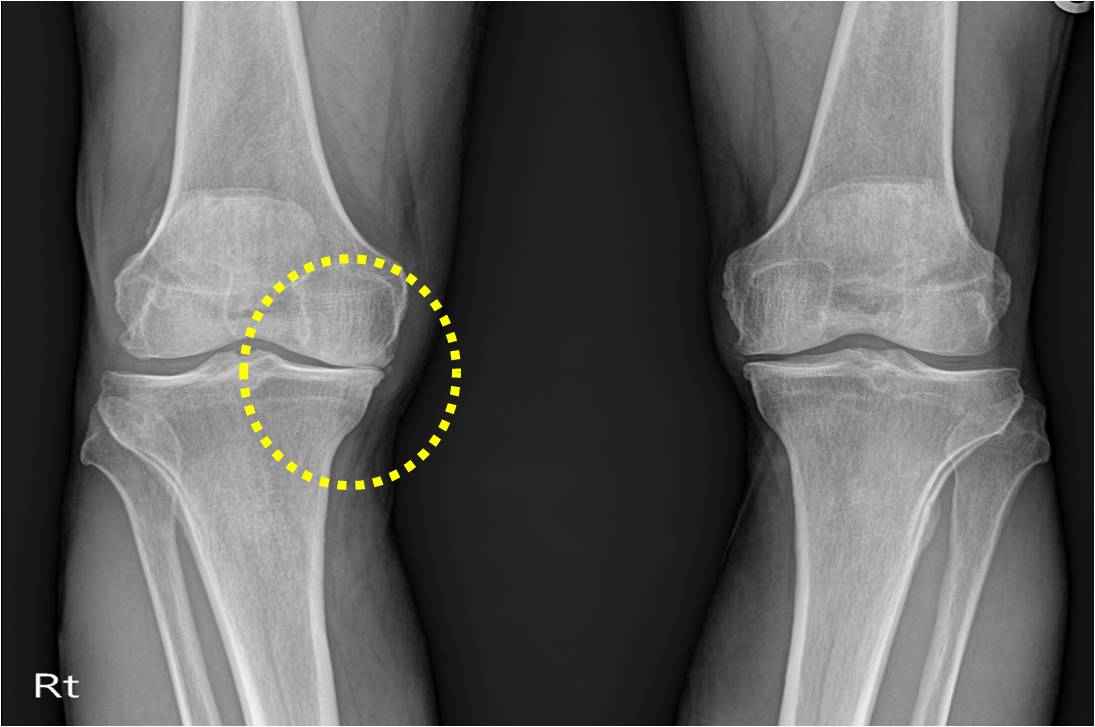

퇴행성 관절염은 나이가 들면서 자연스럽게 발생하는 관절의 마모로 인해 많은 사람들이 고통을 겪고 있는 질환입니다. 통증과 불편함 때문에 일상 생활에 큰 지장을 주기도 합니다.

약물 치료와 수술

심한 경우에는 약물 치료나 수술이 필요할 수 있습니다. 비스테로이드 항염증제(NSAIDs)는 통증과 염증을 줄이는 데 효과적이며, 경우에 따라 스테로이드 주사를 고려할 수 있습니다. 마지막으로, 관절이 심하게 손상된 경우 관절 치환술 같은 수술적 방법이 필요할 수 있습니다. 이러한 방법은 의사와 상담하여 결정하는 것이 중요합니다.